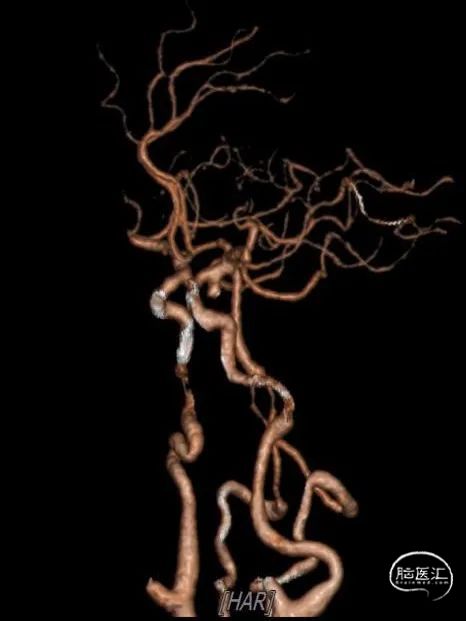

病史简介:患者女性,56岁,主因“发现右侧脑动脉瘤3月余”入院。查体神经系统阴性。3个多月前因“突发头痛、头晕3小时,神志不清2.5小时”伴有呼吸困难。被120送至我院急诊,予以行气管插管。急查CT提示“蛛网膜下腔出血”(图1)。头颅CTA提示“双侧颈内动脉C7段动脉瘤”(图2)。根据动脉瘤形状及CT蛛网膜下腔出血情况判断左侧脑动脉瘤为责任。遂急诊在全麻下行“DSA全脑血管造影术+支架辅助下左侧颈内动脉动脉瘤栓塞术”(图3)。手术经过顺利。术中同时发现右侧颈内动脉颈段冗长,迂曲严重,后交通动脉段亦见一动脉瘤,当时未做治疗。术后行“腰椎穿刺腰大池置管脑脊液引流术”。术后予护胃、营养神经、预防脑血管痉挛、脱水降颅压、抗感染、化痰、控制血压等对症治疗。术后康复出院。

图2

DSA示:右侧颈内动脉后交通动脉段动脉瘤,右侧颈内动脉冗长,迂曲严重,左侧颈内动脉后交通动脉段动脉栓塞术后。